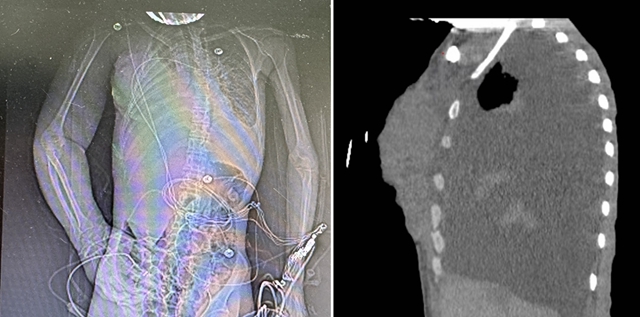

入院时影像检查

“患者入院时体重仅68斤,骨瘦如柴,右上臂肿胀约为左侧1倍,手掌肿胀如馒头,基本丧失握持功能;右侧乳房较正常增大2倍,隆起明显,双侧乳房呈菜花状,溃烂严重。”乳腺·甲状腺·血管外科万霞主治医师介绍。

刘女士入院时呼吸急促、极度虚弱,轻微活动即可导致血氧饱和度急速下降,只能完成床旁检查。床旁彩超提示双侧大量胸腔积液,右侧液层深12cm,左侧10cm,双肺受压明显,呼吸衰竭。万霞医师立即为其行双侧胸腔穿刺置管引流,并予呼吸机支持,呼吸症状暂时得到缓解。检验结果显示:恶病质、重度贫血、呼吸衰竭、酸中毒、肝功能损害,肿瘤标志物显著升高。